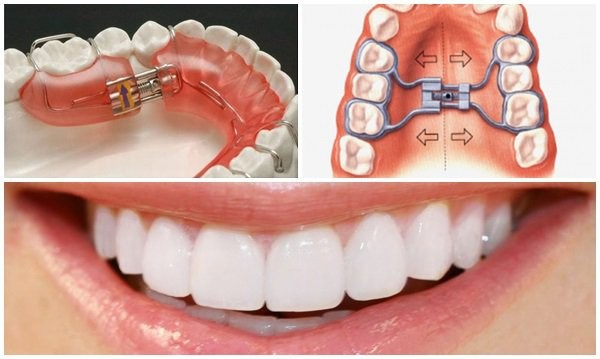

Nong hàm tháo lắp

Đây là phương pháp đơn giản, phù hợp cho trẻ nhỏ hoặc người mới bắt đầu trong quá trình chỉnh hình hàm mặt. Khí cụ nong hàm tháo lắp có thể dễ dàng tháo ra khi cần vệ sinh hoặc trong các giờ ngủ, ăn.

Ưu điểm của kỹ thuật này là dễ thực hiện, giá thành hợp lý và ít gây bất tiện trong sinh hoạt hàng ngày. Bác sĩ sẽ đo đạc kỹ lưỡng mô hình răng để thiết kế khí cụ phù hợp, giúp trẻ dễ dàng chấp nhận.

Tuy nhiên, để đạt được kết quả tốt, bệnh nhân cần tuân thủ chính xác lịch trình đeo khí cụ theo hướng dẫn của bác sĩ. Phương pháp này đặc biệt thích hợp cho các trường hợp nhẹ hoặc khi mới bắt đầu điều trị nong hàm.

Nong hàm cố định

Đây là kỹ thuật sử dụng khí cụ cố định gắn trực tiếp vào răng để duy trì hoặc mở rộng khung hàm lâu dài. Phương pháp này phù hợp với những bệnh nhân cần mở rộng nhanh, cần độ chính xác cao.

Khí cụ cố định giúp hạn chế việc tháo lắp không đúng quy trình, từ đó nâng cao hiệu quả điều trị. Trong quá trình thực hiện, bác sĩ sẽ kiểm tra định kỳ để điều chỉnh khí cụ phù hợp với mức độ mở rộng mong muốn.

Phương pháp này thích hợp cho cả trẻ em và người trưởng thành, đặc biệt khi những phương pháp khác không đạt đủ hiệu quả hoặc bệnh nhân cần kết quả rõ rệt hơn trong thời gian ngắn.